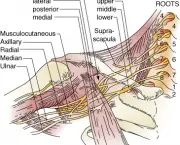

É possível que a dor se espalhe para os ombros e para os braços através dos nervos que se ramificam para longe do peito. Aliás, esse sintoma é que faz com que a Costocondrite se pareça tanto com um problema cardíaco deixando muitas pessoas preocupadas em vão.